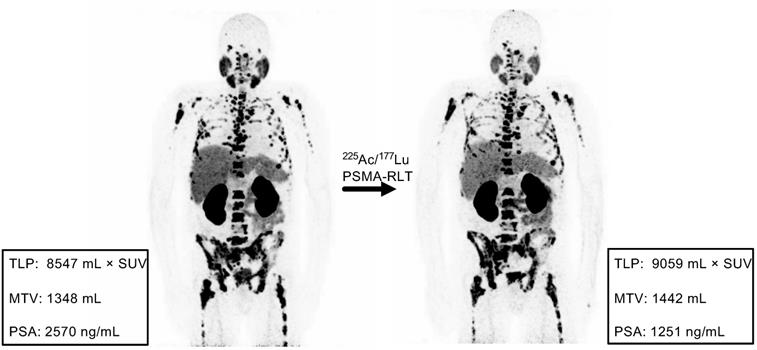

Example of discordance between molecular imaging response assessment (TLP, MTV) and biochemical response assessment (PSA). Patient #11 shows stable disease by TLP (+6%) and MTV (+7%) and partial remission by PSA (-51%).

Comparison of the response assessment methods showed a concordance of 100% (17/17) between TLP and MTV and 70.6% (12/17) between TLP/MTV and PSA (Table 3). Concordant examples of partial remission, stable disease, and progression are shown in Figure 4. Of the discordant patients, two patients had stable disease by molecular imaging but one had partial remission and one had progressive disease by PSA, one patient had partial remission by molecular imaging and stable disease by PSA, and two patients had progressive disease according to molecular imaging but stable disease by PSA (Table 3). A discordant example is presented in Figure 5.